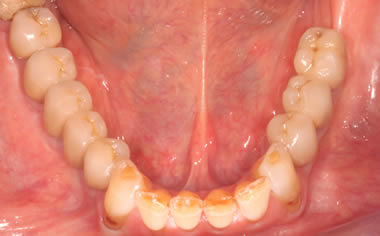

More back teeth replaced by dental implants

Case Three (2 images)

Case Four (4 images)

Case Five (4 images)

Case Six (8 images)

Case Seven (4 images)